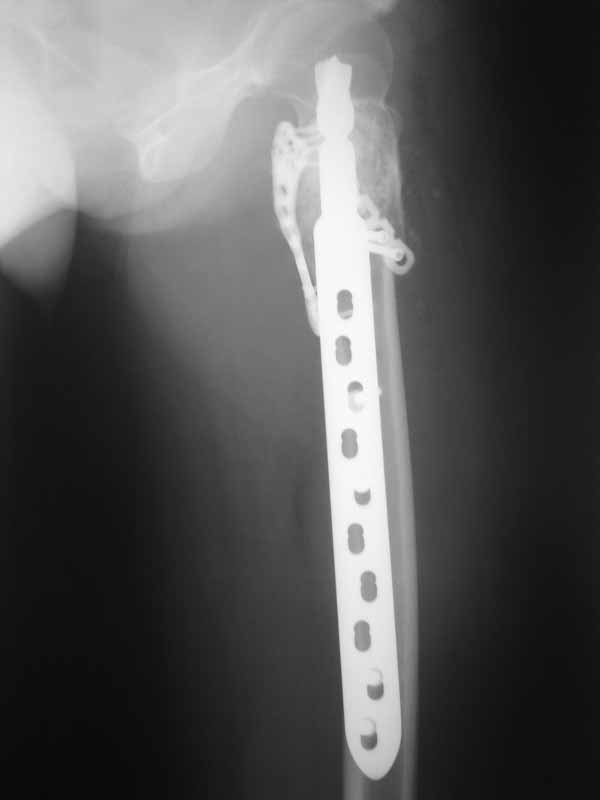

А по пациентке:Обследования провели в легких чисто, лабораторно - без особенностей. Выполнили МРТ - костная киста, однокамерная. Оперирована - створчатая остеотомия, удаление кисты, костная пластика аутокостью с гребня подвздошной кости, остеосинтез DHS со сприральным клинком, створка фиксирована пластинами монокортикально.

Макроскопически - слизеподобное содержимое темно-бурого цвета, отдали на гистологию.